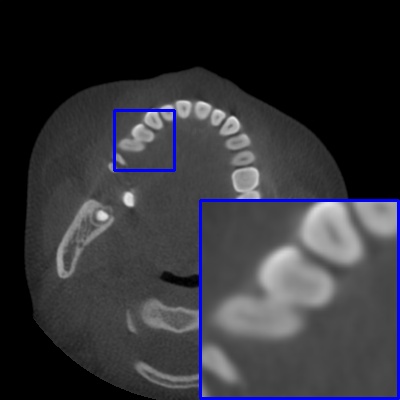

Figure 4: Comparison of MAR images by different methods on real-world MA image. The last image is the metal mask by selecting the pixel area over 2800HU in the MA image.

Results on real-world MAR. We also compare these methods on dental CBCT images with real-world metal artifacts. The visual results on one sample are shown in Fig. 4. We observe that our MARformer-T and MARformer-L well seperate the adjacent teeth and retain their shapes. This shows that our MARformers, though trained on synthetic data, are effective on real-world MAR.